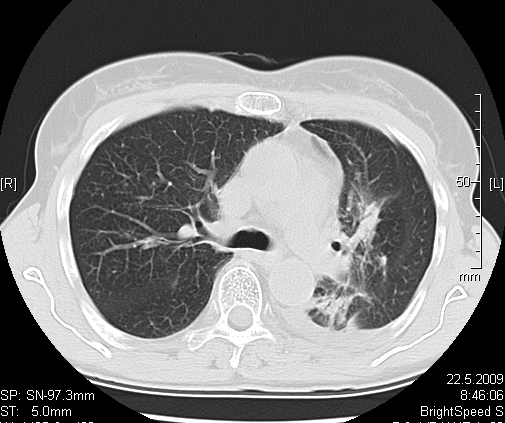

Foto: Aleksandar Ivković Foto: Aleksandar Ivković Foto: Aleksandar Ivković Strašna razlika kod pluća pušača i kovid pozitivne osobe autor: Božica Luković Zdravlje 23. jan. 2021. 12:06 > 23. jan. 2021. 12:15 0 Podeli vest: Radiolog Aleksandar Ivković od početka pandemije daje korisne informacije o svim aspektima kovida 19. On je nedavno uporedio rendgen snimke pluća zdrave osobe, pušača, osobe koja je zaražena gripom H1N1, a onda i osobe koja ima kovid 19. Razlike su zapanjujuće. Podeli vest: Oglas Objavu doktora Ivkovića sa njegovog bloga "Ljudi i ostale laži" prenosimo u celosti."Nedavno sam video u medijima da je neko preneo rdg sliku i razlike kod nalaza zdrave osobe, pušača i bolesnog od kovida 19. Kako nisam baš previše zadovoljan onim što je prikazano, evo kako to izgleda u našoj varijanti. Zdrava osoba CT nalaz kod zdrave osobe podrazumeva da ne postoje nikakvi poremećaji strukture plućnog parenhima, da su krvni sudovi uredni i da nema suženja disajnih puteva, kao i da nema uvećanih limfnih žlezda u hilusima pluća i medijastinumu. Foto: Aleksandar Ivković | Foto: Aleksandar Ivković * Foto: Aleksandar Ivković | Foto: Aleksandar Ivković Zdrava muška osoba mesec dana nakon zapaljenja pluća tokom kovida 19. Nalaz bez nekih posebnih problema iako se naziru tragovi zapaljenja. Snimak u boji je zdrava osoba, nepušač, bez ikakvih bolesti pluća u istoriji. Grip H1N1 Pokazaću samo drastične nalaze kod gripa H1N1, to je znači onaj grip koji je izazvao epidemiju španske groznice i epidemiju 2009. godine koja još uvek nije prestala (svake godine imamo makar 15%). Foto: Aleksandar Ivković | Foto: Aleksandar Ivković * Foto: Aleksandar Ivković | Foto: Aleksandar Ivković * Foto: Aleksandar Ivković | Foto: Aleksandar Ivković * Foto: Aleksandar Ivković | Foto: Aleksandar Ivković Nisu svi pacijenti imali ovakve nalaze, pokazujem one koji su imali tešku kliničku sliku. Kod gripa se sve odvija obično u sedam dana. Kao što se vidi, zapaljenje je bilo jednostrano, uglavnom. Ali kada je dolazilo do pogoršanja, onda je centralno obostrano dolazilo do edema pluća. Pušenje Kod pušača postoje razne varijante nalaza na plućima. U principu nisu tako dramatične kao što su zapaljenja. Nalaz na plućima kod pušača može biti potpuno normalan. Ovo ne pišem zato što podržavam pušenje, naprotiv, veliki sam protivnik, ali iznošenje laži nikada nije dobro. Dve dijagnoze su bitne kao posledica pušenja. Prva je hronična plućna opstruktivna bolest: Foto: Aleksandar Ivković | Foto: Aleksandar Ivković * Foto: Aleksandar Ivković | Foto: Aleksandar Ivković * Foto: Aleksandar Ivković | Foto: Aleksandar Ivković Jasna je razlika u nalazu, posebno na ovim slikama u boji, gde su ta plava polja delovi pluća koji su propali zbog cigareta (može da se uporedi sa zdravim plućima iznad).Druga bolest koja je česta kod pušača je u svakom slučaju karcinom. Foto: Aleksandar Ivković | Foto: Aleksandar Ivković * Foto: Aleksandar Ivković | Foto: Aleksandar Ivković * Foto: Aleksandar Ivković | Foto: Aleksandar Ivković * Foto: Aleksandar Ivković | Foto: Aleksandar Ivković Tkivo koje raste unutar pluća i razjeda ga. Takav je nalaz kod karcinoma pluća. Često je uzrok upotreba cigareta. Kovid 19 O kovidu sam pisao puno puta. Evo nekih slika, radi poređenja. Foto: Aleksandar Ivković | Foto: Aleksandar Ivković * Foto: Aleksandar Ivković | Foto: Aleksandar Ivković * Foto: Aleksandar Ivković | Foto: Aleksandar Ivković * Foto: Aleksandar Ivković | Foto: Aleksandar Ivković Nakon što pacijent bude izlečen od gripa ili kovida 19, pluća se mogu vratiti u normalu.To je razlika u odnosu na posledice upotrebe cigareta. Ovi snimci nisu postavljeni da bi se poredile bolesti, već da bi se ukazalo kako različite bolesti deluju na pluća. I ono što je veoma važno, ako neko dobije jednu od ovih bolesti, ne znači da u toku života neće dobiti drugu.Ne pišem zato smo smatram da sam najpametniji ili najpozvaniji da objašnjavam, nisam kao neki pojedinci ubeđen da samo ja imam znanje i istinu, pišem jer drugi ćute. Pišem jer ima i puno onih koji iznose laži, mora se tome stati na put.A ovi, koji pišu da sam umro, da sam oboleo od karcinoma, ovi koji mi žele da nađem dobro grobno mesto, šta da vam kažem, vi ste mi inspiracija. Svesni ste da sam u pravu i odlično znam da ste već uradili sve da se vakcinišete i mnogi od vas će to uraditi pre mene ali i dalje ćete ubeđivati druge da se ne vakcinišu i da je dobro za njih da se razbole i umru. Ima puno reči za vas u svim našim slovenskim jezicima, znate vi sami šta ste", piše dr Ivković.***Bonus video:https://youtu.be/MWucTT0qBsIPratite nas i na društvenim mrežama:FacebookTwitterInstagram Dr Lukić otkrio spisak svih antibiotika za kovid upalu pluća Zdravlje 0 Dr Žujović: Kako oporaviti pluća posle korone Zdravlje 0 Pet znakova da ti je kovid zahvatio pluća Zdravlje 0 Virusolog Ana Banko ruši veliku zabludu o ruskoj vakcini Emisije 0 aleksandar ivković korona kovid pluća snimak pluća Pratite nas na društvenim mrežama: Koje je tvoje mišljenje o ovoj temi? Učestvuj u diskusiji ili pročitaj komentare Budite prvi koji će ostaviti komentar Pošalji komentar Pročitaj komentare (0)